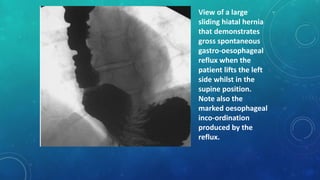

View of a large

sliding hiatal hernia

that demonstrates

gross spontaneous

gastro-oesophageal

reflux when the

patient lifts the left

side whilst in the

supine position.

Note also the

marked oesophageal

inco-ordination

produced by the

reflux.